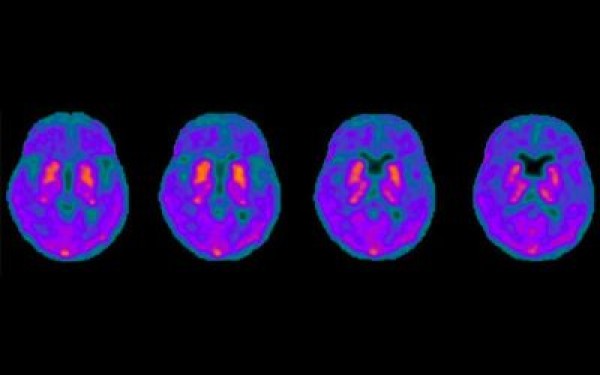

- In PET we offer the use of new and novel tracers and were the first in New Zealand to scan and report utilising tracers

PET imaging key to understanding Parkinson's disease dementia

A unique research study is underway through the New Zealand Brain Research Institute (NZBRI) with New Zealand’s first brain tau PET scan in Christchurch. The focus is on Parkinson’s disease dementia.